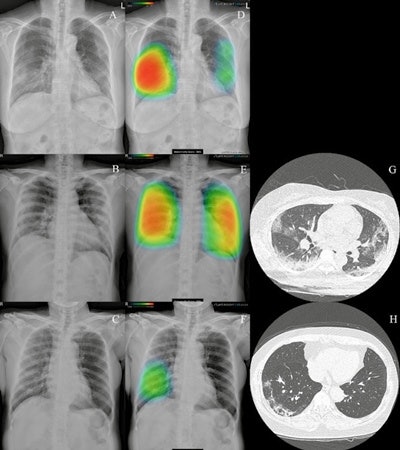

Artificial intelligence (AI) software developer Lunit is touting the results of a recent PLOS One study showing that its Insight CXR algorithm successfully detected COVID-19 pneumonia on chest radiography.

The November 24 study compared the clinical effectiveness of the algorithm with formal radiology reports using COVID-19 cases from five medical institutions in South Korea. Researchers included chest x-rays from 279 patients in the analysis, Lunit noted.

Lunit reported that Insight CXR achieved a 95.6% sensitivity and 88.7% specificity for detecting COVID-19 from the radiographs. The algorithm also showed no significant difference in area under the curve values compared with radiology reports, according to the company.